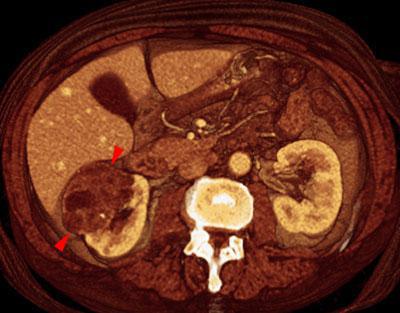

Nefroma quístico multilocular

VR seccional. Visión axial caudal. TC contrastado en fase venosa que muestra lesión quística encapsulada y multiloculada (puntas de flecha) que se extiende hacia el hilio renal